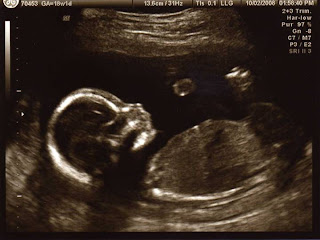

Ron @ 18 weeks 1 day